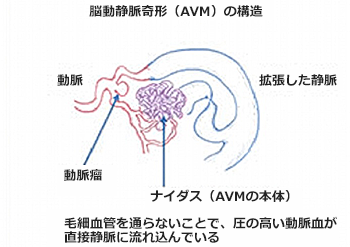

先天的な病気と言われており、母体にいるときから、既に形成されていると考えられています。本来、人間の血管の構造には、大きく分けて「動脈」と「静脈」があります。心臓から酸素をたっぷり含んだ血液は、「動脈」を通って、脳、腎臓、肝臓などの臓器に送られ、臓器の中の「毛細血管」という構造に入ります。ここで組織に酸素を送り、不要な二酸化炭素を吸収しながら、「静脈」へと流れ、心臓に血液が戻っていきます。また、この「毛細血管」を血液が通ることにより、「動脈」を通ってきた血液の圧が下がり、「静脈」を流れる血液の圧が低くなります。AVMにおいては、脳の血管構造の一部で、「毛細血管」を介さずに「ナイダス」と呼ばれる異常な血管網を介して、「動脈」と「静脈」が交通しています。このために、本来は低圧系である「静脈」の中を圧が下がっていない「動脈血」が流れる状態になっています。このために、高圧に慣れていない「静脈」が拡張して太くなったり、静脈瘤を形成して破裂をしたりすることで、脳出血やくも膜下出血を来すことがあります。また、AVMの部分は、血流が非常に多く早くなるため、周囲の正常脳への血流を奪い取ってしまうことがあり、これによる正常脳の慢性的な血流低下をきたし、二次的に脳組織の変性を来たし、痙攣発作を起こすこともあります。